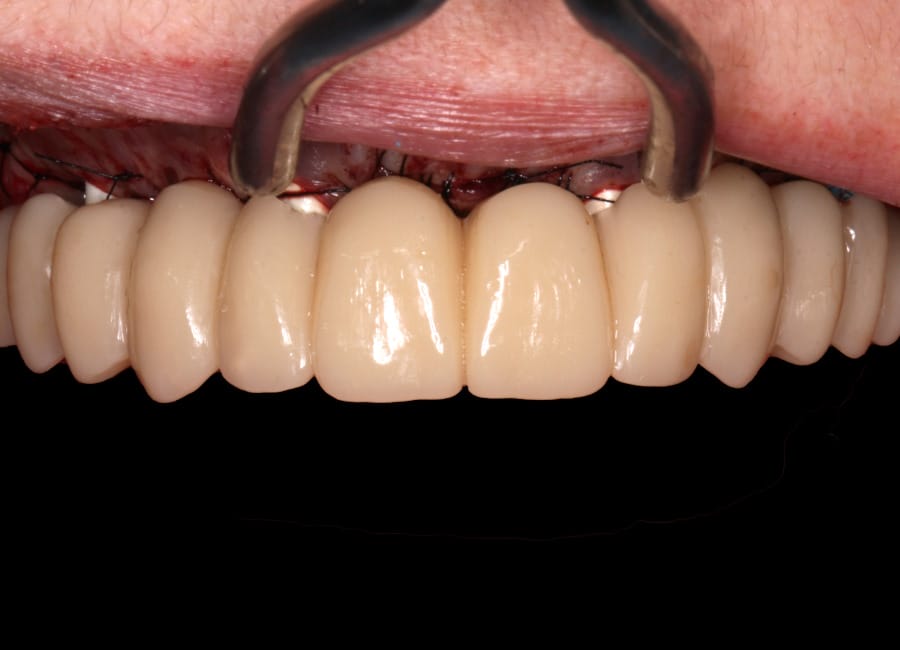

All data were transferred into digital treatment planning software, allowing virtual placement of implants and collaboration with the dental laboratory before surgery. This enabled careful evaluation of long-term outcomes and ensured the design of provisional and final prosthetics could be completed with precision. Following these discussions, the decision was made to proceed with the Fixed-Teeth-in-a-Day approach using the All-on-4 technique.

Surgical phase

The moment Natalie saw her new smile, the emotion was undeniable. What had once been a source of discomfort, anxiety, and embarrassment had been completely transformed. Her new teeth restored full function and aesthetics, giving her back the ability to eat, speak, and smile without hesitation.